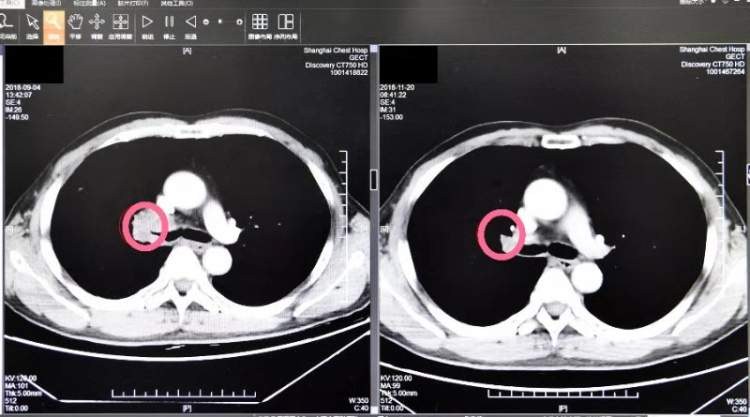

在胸科医院肿瘤科陆舜主任的带领下,由肿瘤科(内科、外科)、放射科、病理科等组成的团队,经过多次研讨和会诊,在一个月内,通过免疫治疗方法,蒋老伯肺里的肿瘤从原来的4.2公分缩小到了2.8公分,整整减少了30%!手术指征有了!

这一个月里,作为蒋老伯在免疫治疗阶段的负责医生,肿瘤科主任医师周箴团队对他的病情进行了密切细致的诊治和观察。30天的治疗后,专家们欣喜地发现老人的肿瘤组织明显缩小,肺动脉侵犯减少,虽然手术难度还是很大,但各项指征都已经符合标准,得知消息的蒋老伯激动不已,他做梦也没想到在那么短的时间里自己竟然有了做手术的机会。且和化放疗相比,免疫治疗基本没有毒副反应,蒋老伯感觉体力棒棒哒,完全能够承受手术。